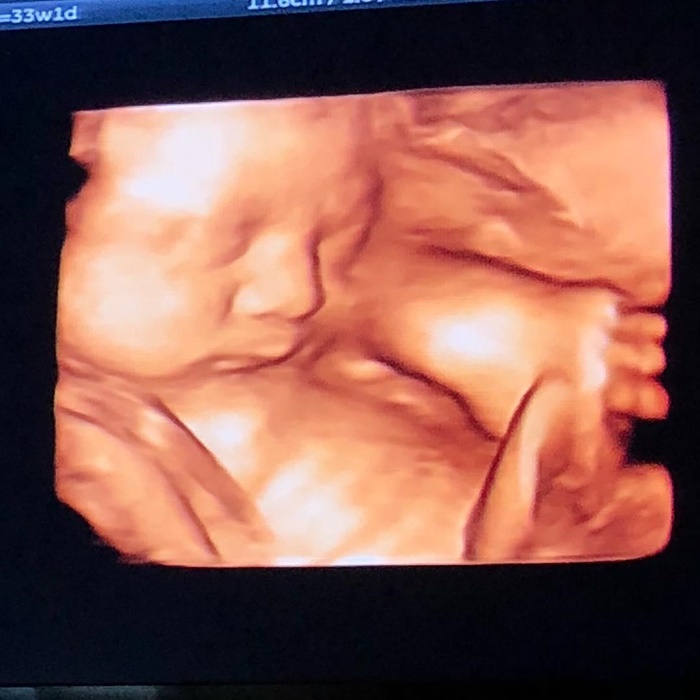

อีกไม่นานก็ใกล้จะได้เห็นหน้าเบบี๋น้อยลูกชายของคุณแม่ กระแต ศุภักษร แล้ว โดยล่าสุด (20 เมษายน 2561) คุณแม่กระแต ได้โพสต์ภาพอัลตราซาวด์ลูกชายตัวน้อยในครรภ์ 33 สัปดาห์ ให้แฟนคลับได้ยลโฉมกันแล้ว

งานนี้บอกเลยว่า เบบี๋น้อยมีแววความหล่อออร่าพุ่งมาแต่ไกลเลย อีกไม่นานก็ใกล้จะได้ยลโฉมลูกชายคุณแม่กระแต กันชัด ๆ แล้ว อดใจรอกันหน่อยนะจ๊ะพี่ ๆ จ๋า